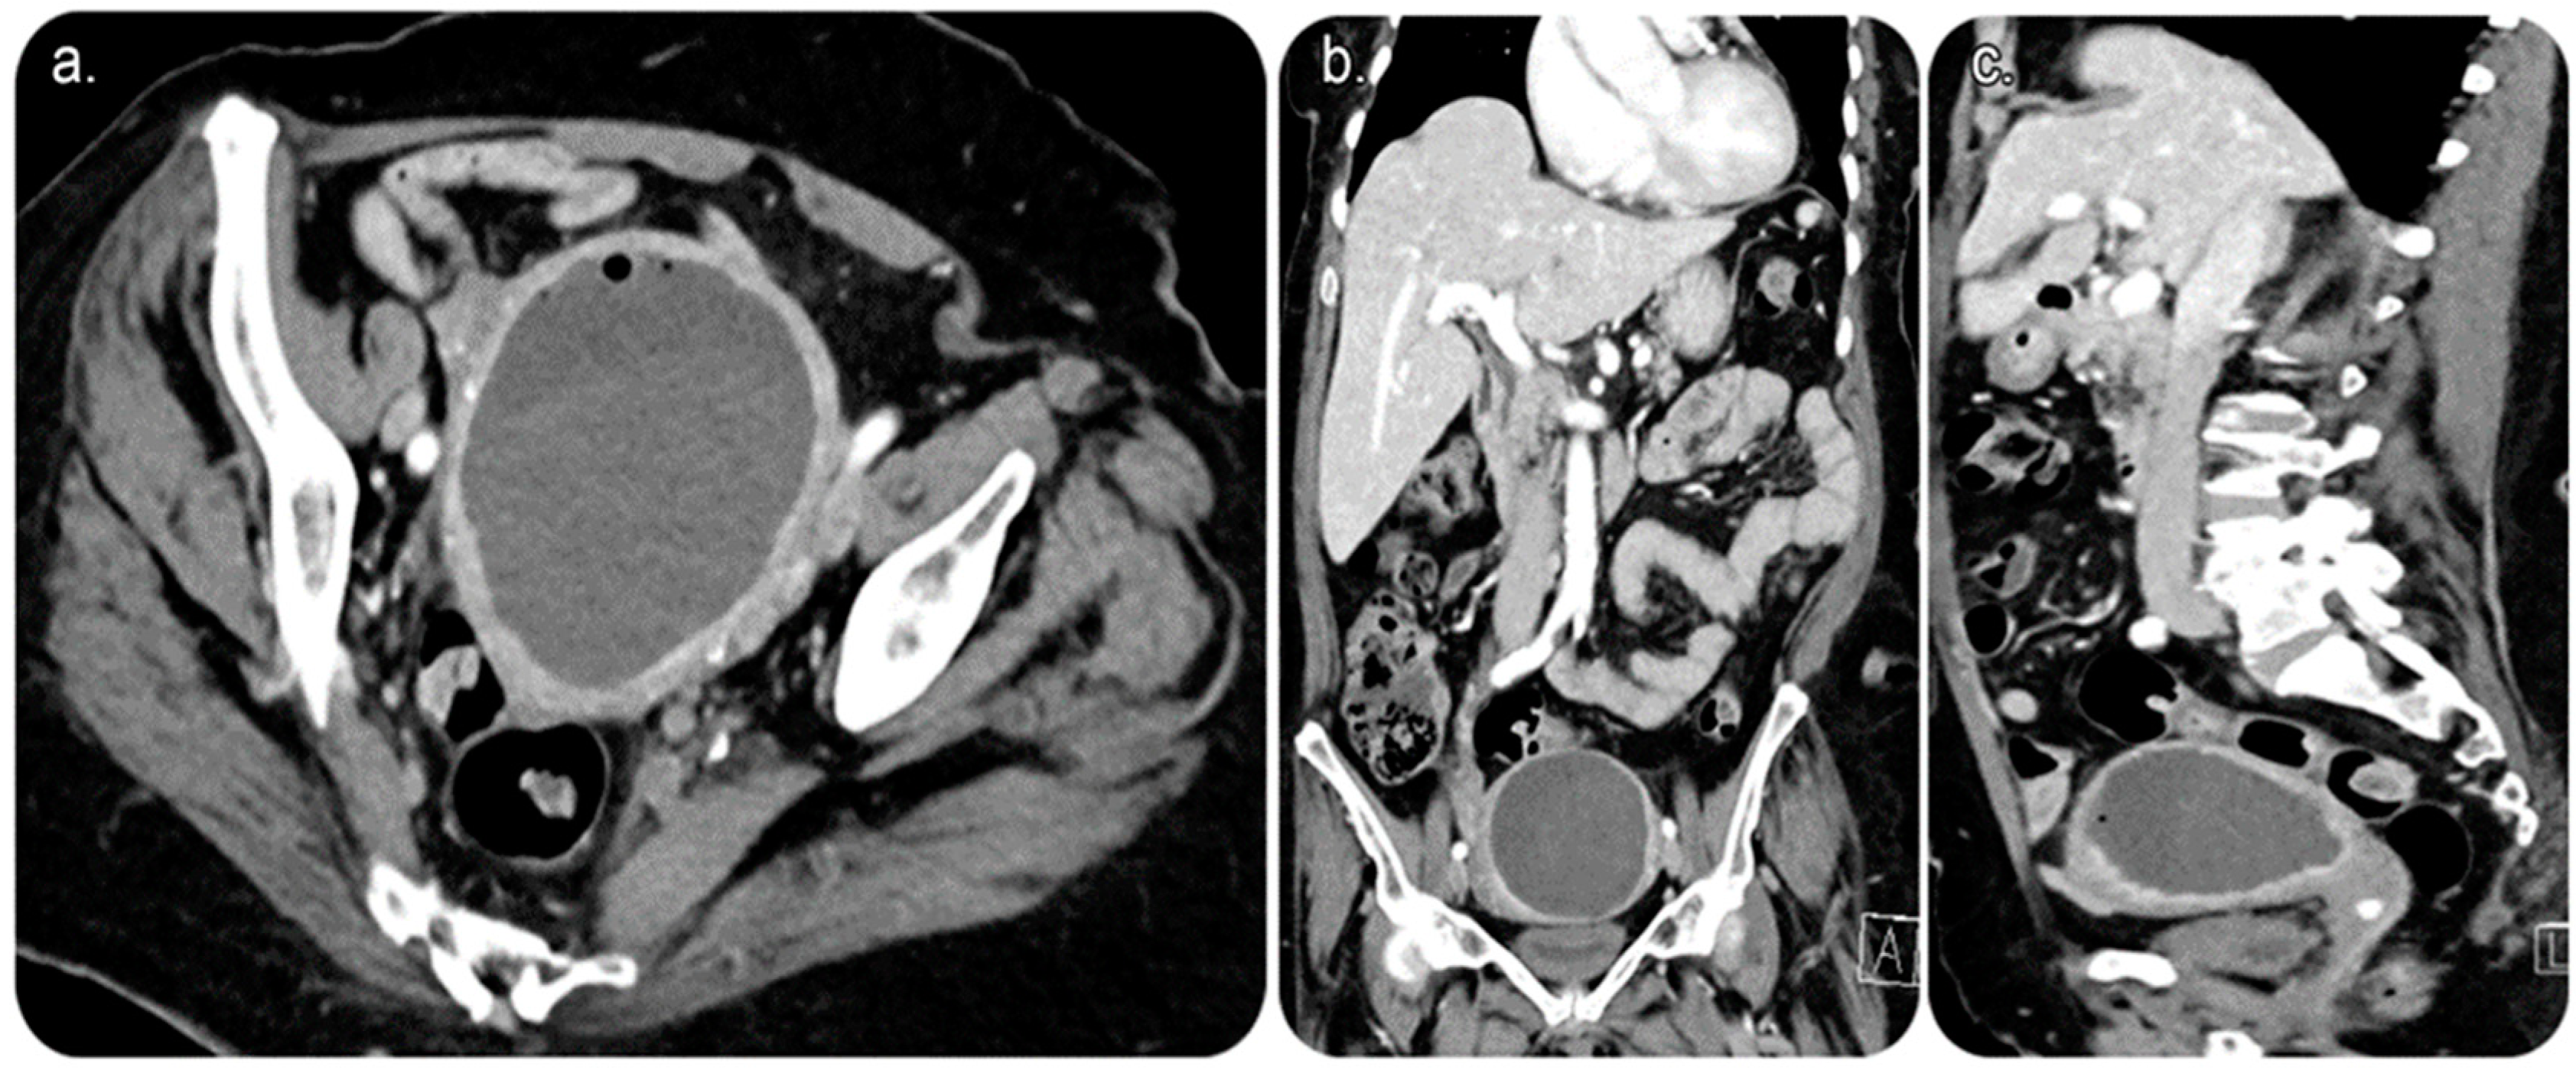

CT of the abdomen and pelvis with intravenous (IV) contrast revealed a sizable endometrial cavity collection with air foci, faint fluid–fluid levelling, and irregular endometrial enhancement. Moreover, an enhanced cervical lesion was identified (Figure 1). Her laboratory results indicated a slight increase in white blood cell count; however, other test results were within the normal range. Pap smear and human papillomavirus tests indicated no evidence of malignancy.

Day 1 post-procedure, the patient underwent an ultrasound scan, which revealed significant improvement in the endometrial fluid collection. The patient was taken to an Angio Suite, wherein a wire was advanced through the pre-existing drainage catheter that was inserted in a retrograde fashion. Thus, the fluid collection was diverted through the vagina outside the body. The percutaneous drain was removed and replaced after advancing the wire through the cervix until it exited outside the vagina, with another transvaginal catheter inserted over the wire using a similar concept of body flossing technique (Figure 4).

Figure 1. Reformatted computed tomography (CT) images of the abdomen and pelvis with (intravenous) IV contrast. (a) Axial cut CT of the pelvis showing an endometrial fluid collection with air focus at the non-dependent part of the endometrium. The endometrial lining shows an evident contrast enhancement. No CT evidence of anterior abdominal scar is seen, proving no prior history of Caesarean birth. (b) Coronal and (c) sagittal CT of the abdomen and pelvis showing endometrial fluid collection with an air focus at the non-dependent part of the endometrium.